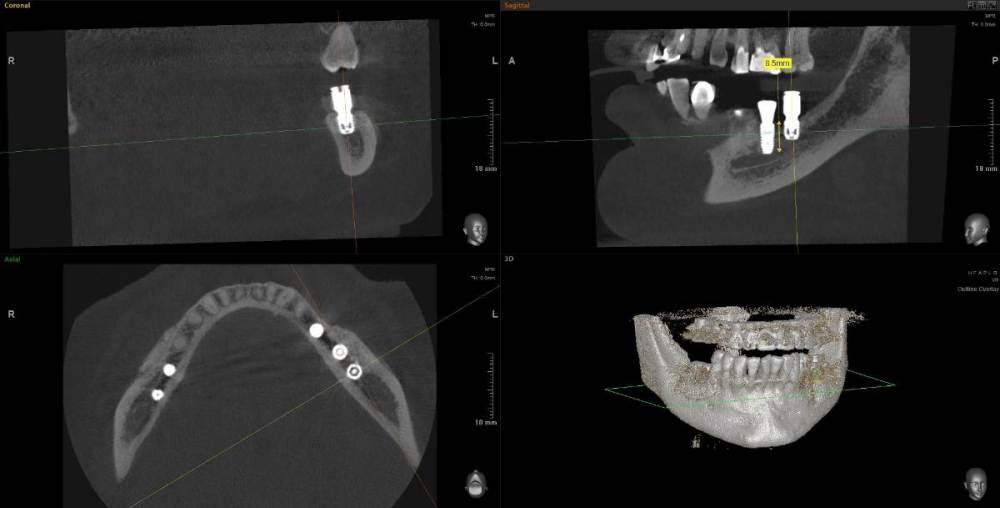

Kostoprav Опубликовано 11 мая, 2021 Поделиться Опубликовано 11 мая, 2021 (изменено) 70%ауто+30% ксено, мембрана цитофлекс, винты самосверлящие после пластики до установки имплантов прошло 8 мес. Изменено 11 мая, 2021 пользователем Kostoprav 3 6 Ссылка на комментарий

Карен Аванесов Опубликовано 12 мая, 2021 Поделиться Опубликовано 12 мая, 2021 20 часов назад, Kostoprav сказал: 70%ауто+30% ксено, мембрана цитофлекс, винты самосверлящие после пластики до установки имплантов прошло 8 мес. Замечательно! 1 Ссылка на комментарий